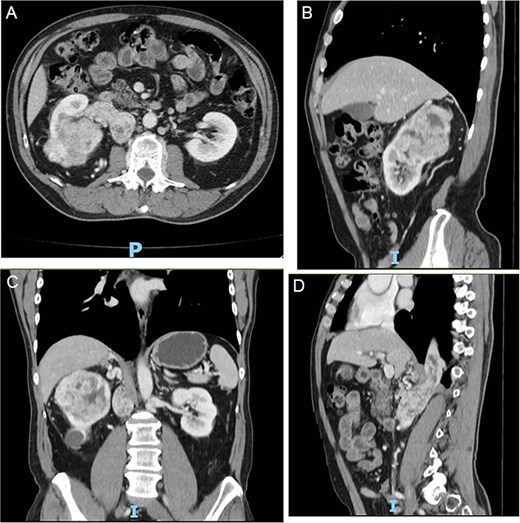

Follow-up CT imaging (Fig. 3A–D) showed a reduction in both the tumor and thrombus size, leading to the classification of the thrombus from Stage IV to Stage III according to the Mayo Clinic classification.

(A–D) Abdominopelvic contrast-enhanced computed tomography post-neoadjuvant therapy showed a significant reduction in tumor size and the involvement of the thrombus in the azygos vein.